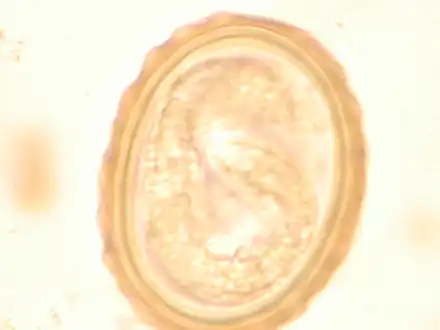

Ascaris lumbricoides adult worms Ascaris egg, incubation process: The Ascaris egg incubation process consists of placing the egg in a controlled environment, at 26 °C (79 °F) during 28 days, in acidic conditions. This process allows for the evaluation of an egg to determine if it is viable or not.

Ascaris egg, incubation process: The Ascaris egg incubation process consists of placing the egg in a controlled environment, at 26 °C (79 °F) during 28 days, in acidic conditions. This process allows for the evaluation of an egg to determine if it is viable or not.

Diagnosis

Most diagnoses are made by identifying the appearance of the worm or eggs in feces. Due to the large quantity of eggs laid, diagnosis can generally be made using only one or two fecal smears.[31] The diagnosis is usually incidental when the host passes a worm in the stool or vomit. The eggs can be seen in a smear of fresh feces examined on a glass slide under a microscope and there are various techniques to concentrate them first or increase their visibility, such as the ether sedimentation method or the Kato technique. The eggs have a characteristic shape: they are oval with a thick, mamillated shell (covered with rounded mounds or lumps), measuring 35–50 micrometer in diameter and 40–70 in length. During pulmonary disease, larvae may be found in fluids aspirated from the lungs. White blood cell counts may demonstrate peripheral eosinophilia; this is common in many parasitic infections and is not specific to ascariasis. On X-ray, 15–35 cm long filling defects, sometimes with whirled appearance (bolus of worms).